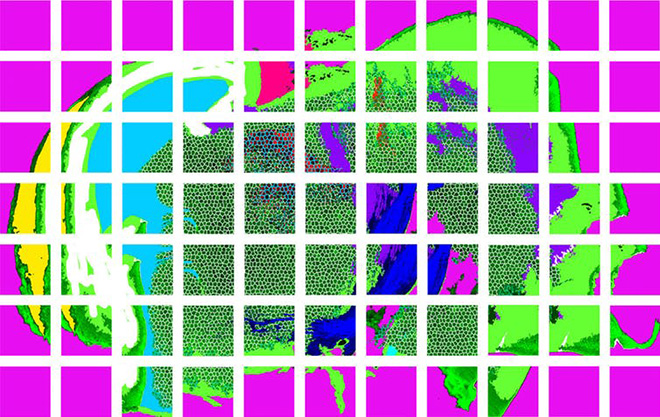

MRI images of the human brain

MRI images of the human brain Chase Sherwell/QBI, Author provided

As neuroscience becomes increasingly of public interest, researchers are striving to make their findings accessible, with parallels to the pop art movement. These are MRI images of the human brain.